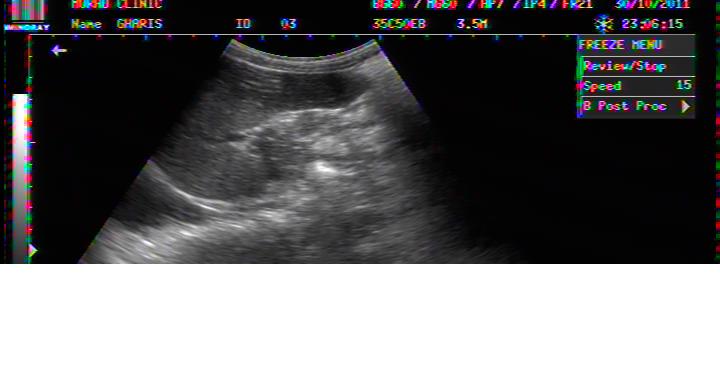

PERICHOLECYSTIC FLUID COLLECTION IN DHF

ROLE OF ULTRASOUND IN EARLY DIAGNOSIS OF DHF.

EARLY DETECTION OF PLASMA LEAK INTO PERITONEAL OR PLEURAL CAVITY